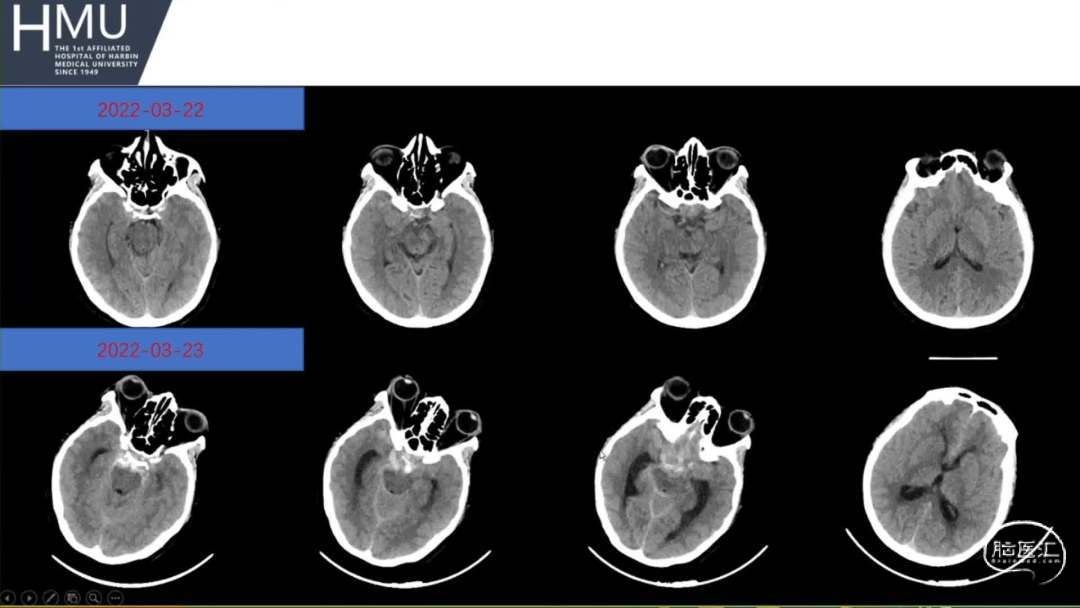

23日06:00

患者答非所问,查体不配合

急行头部CT

23日14:00患者刺痛不睁眼,不发声,

右上肢刺痛定位,左侧瞳孔光反射消失。